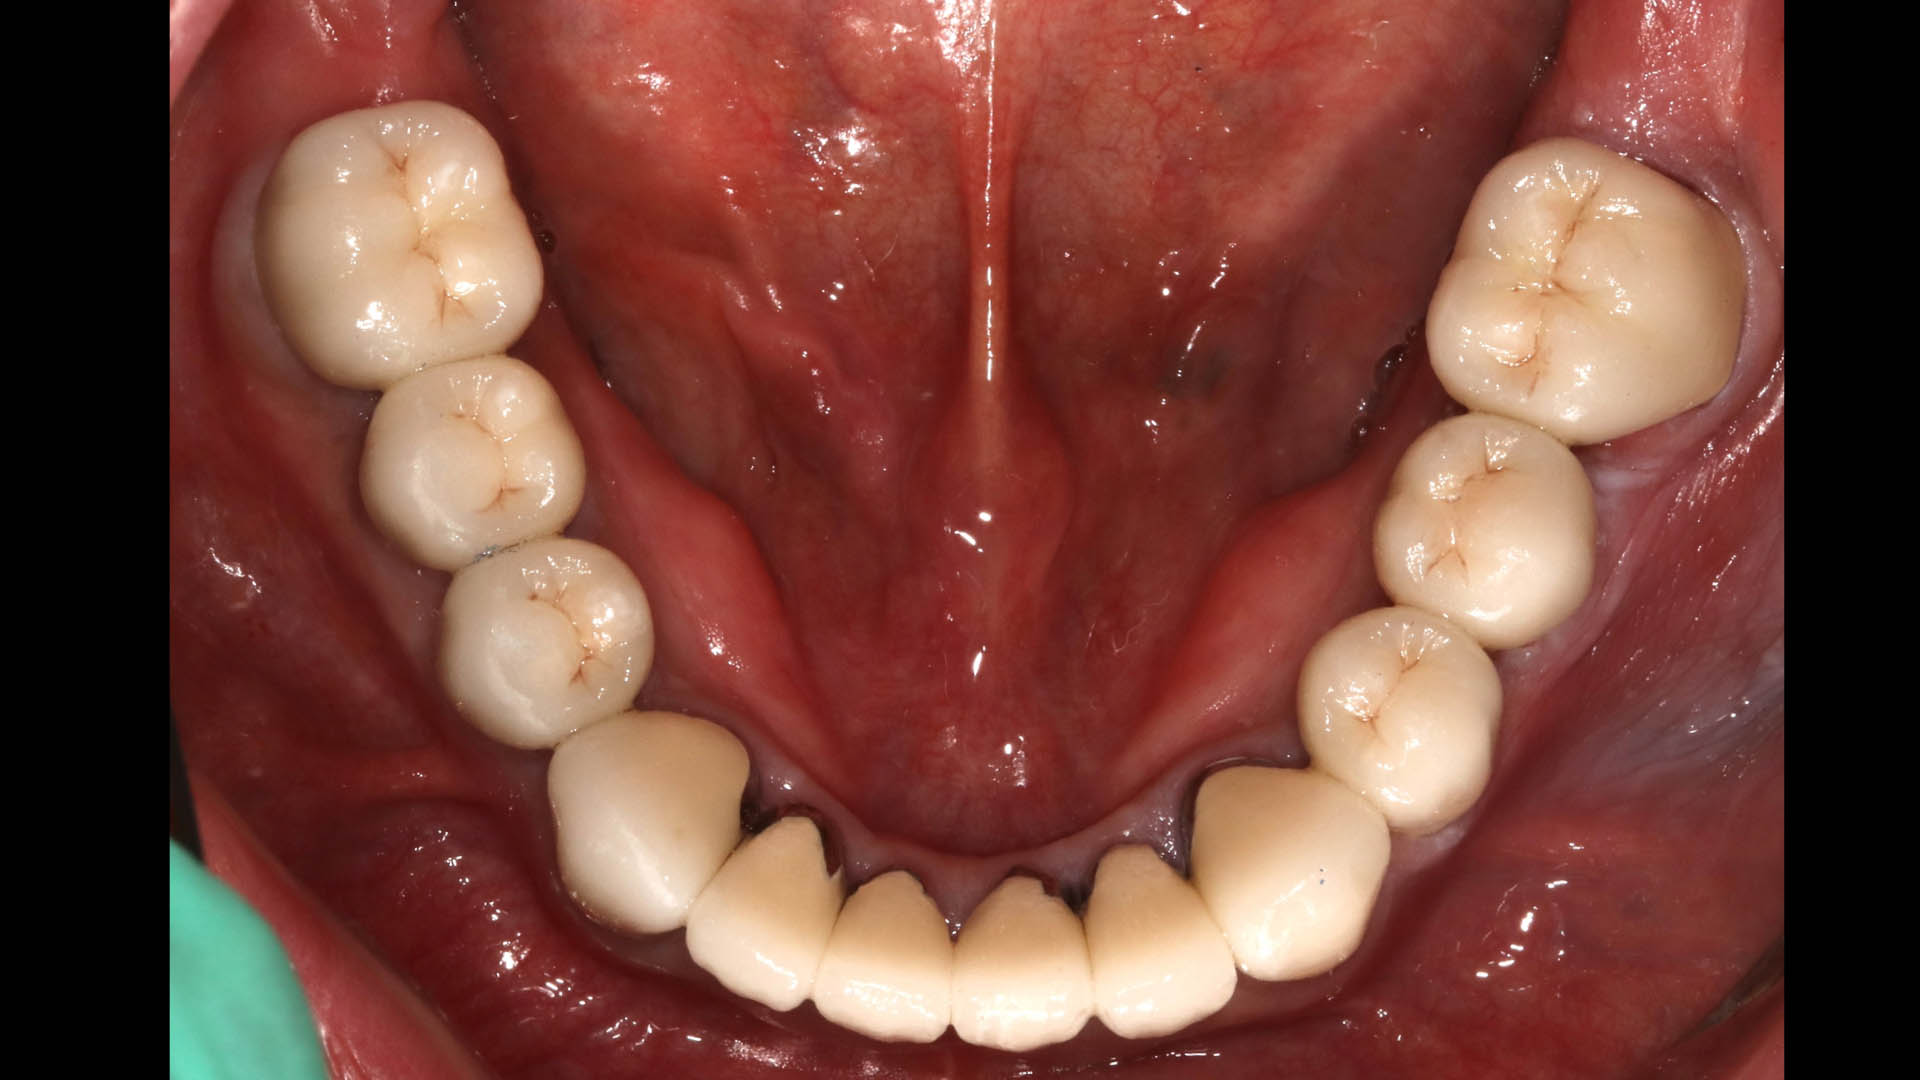

Take a glimpse into the magic of Coral Gables Dentistry through our before and after pictures. See firsthand the incredible smile makeover transformations that have brought confidence and joy to our patients.